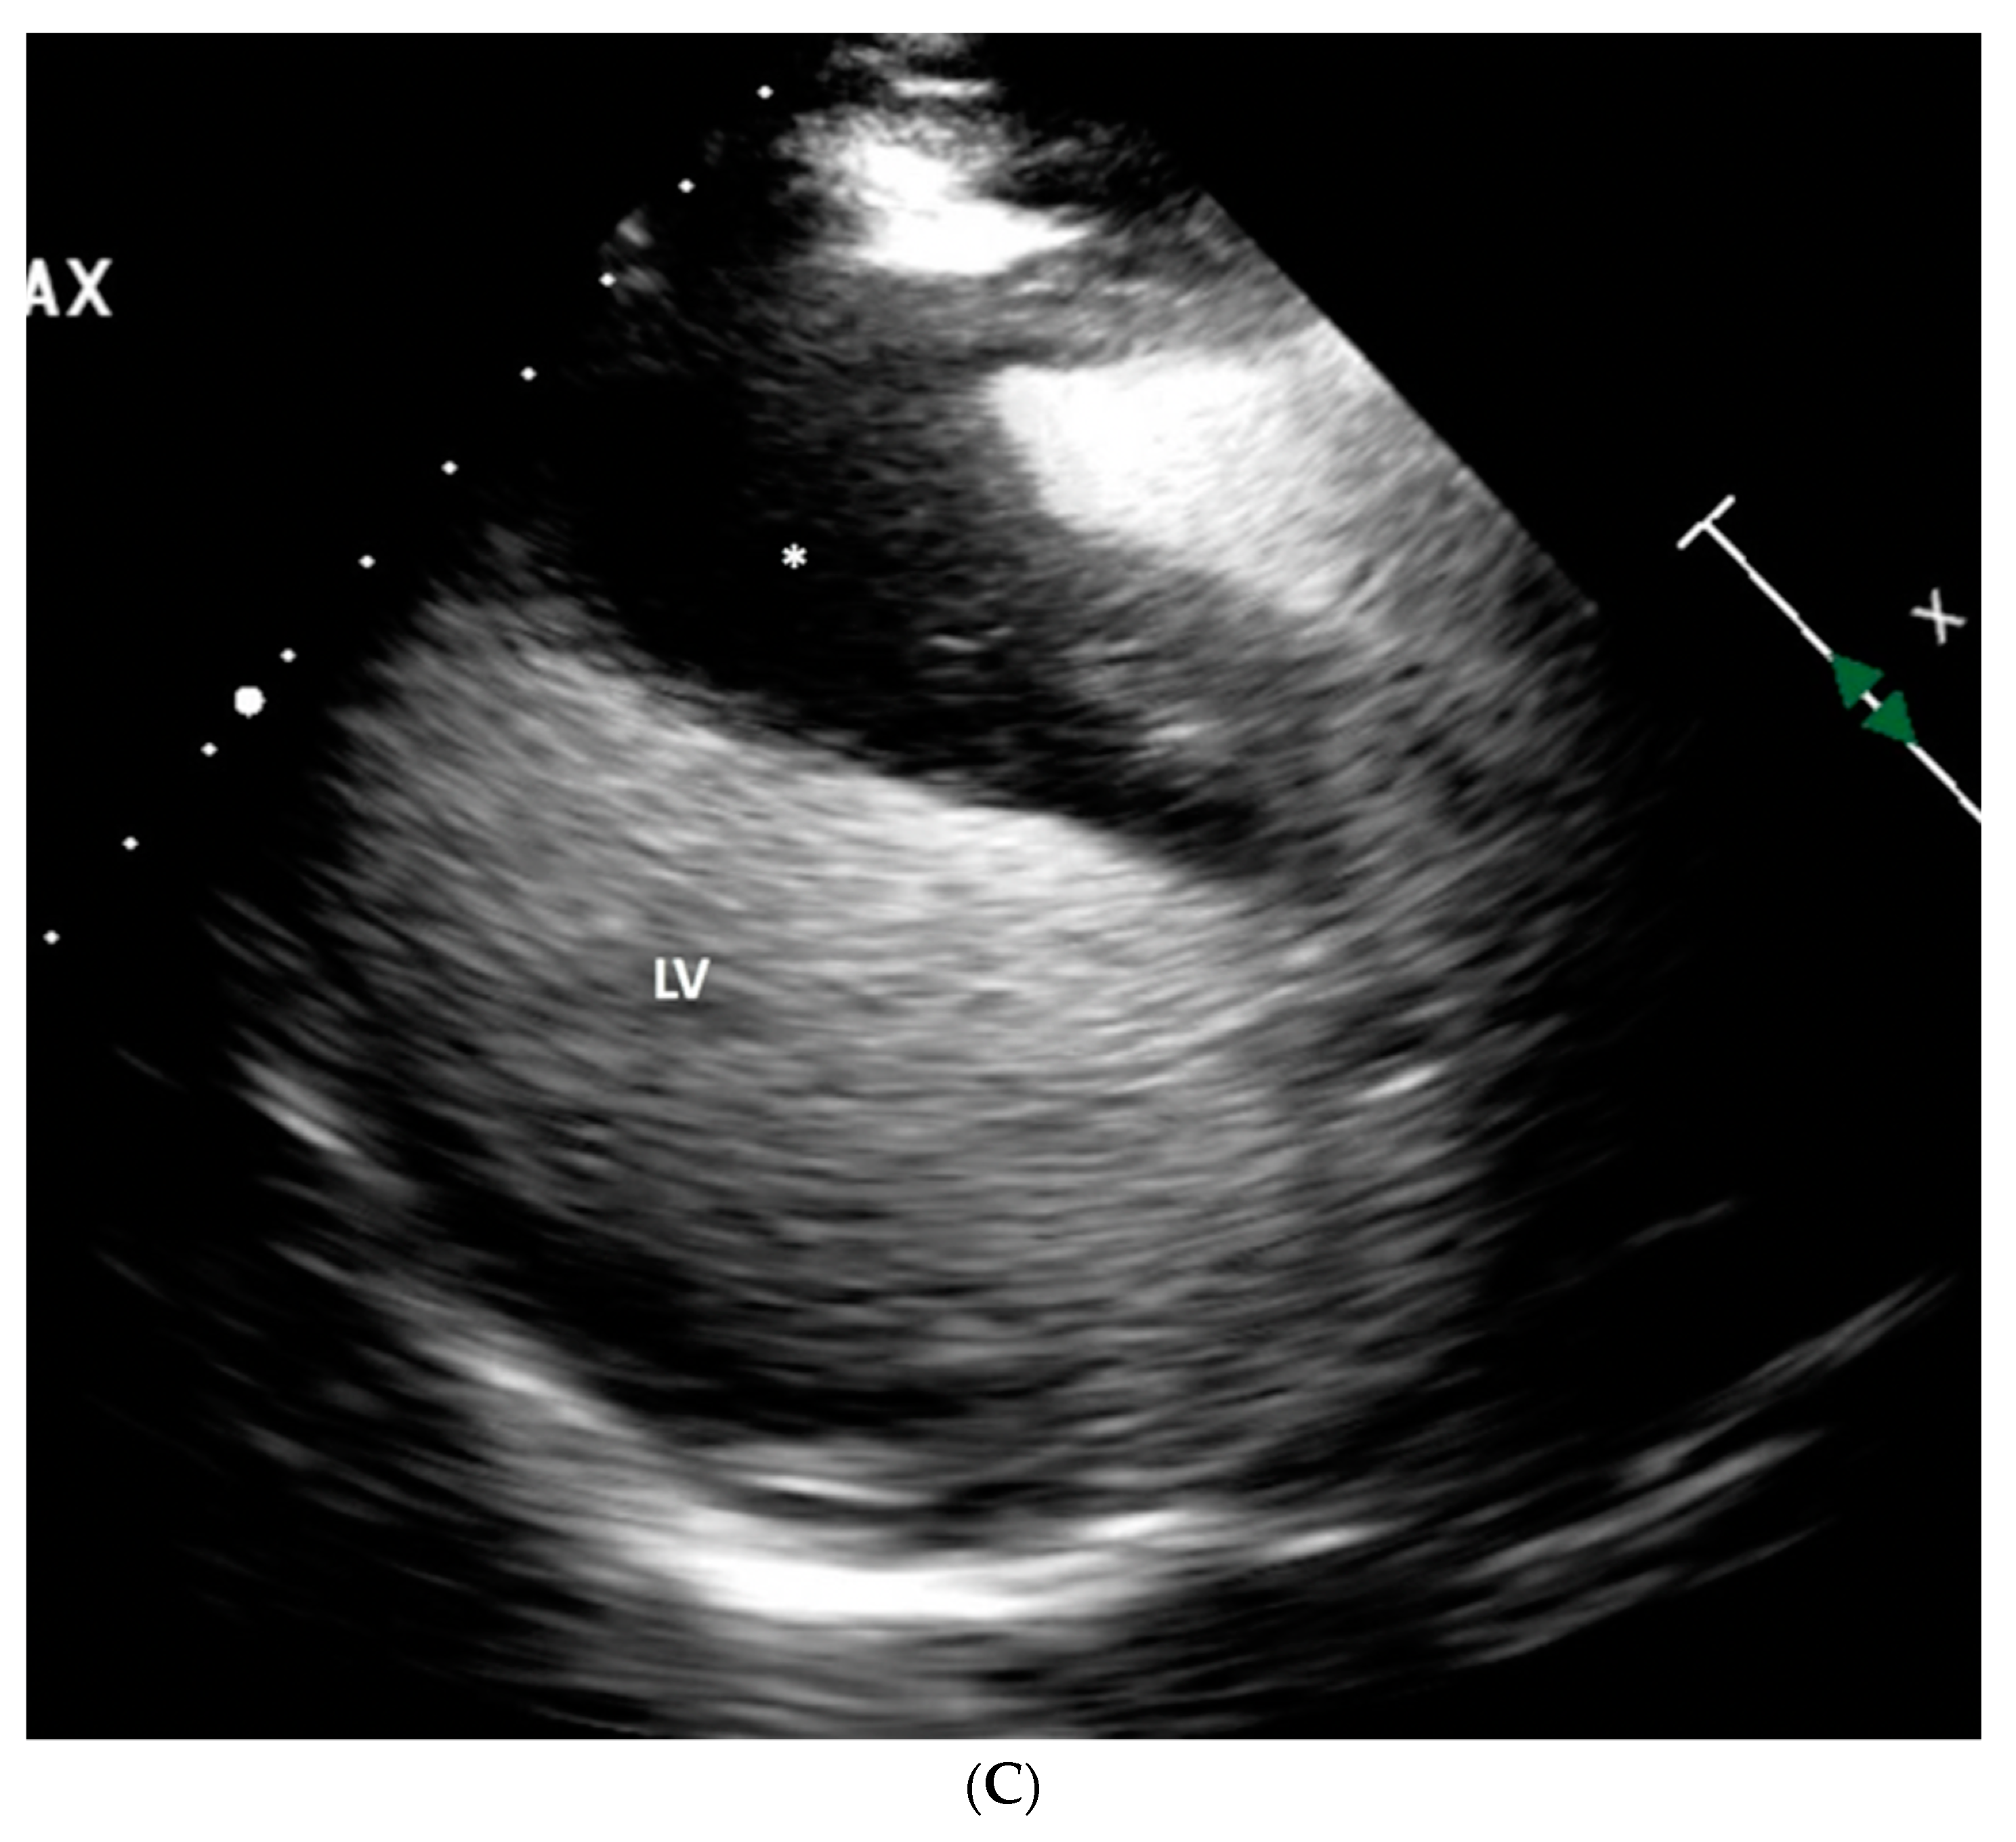

The angiographic findings suggested external compression as the likely cause of the 80% lesion in the mid LAD. This assumption gained credence when considering the non-invasive imaging results. Transthoracic echocardiogram showed normal left ventricular chamber diameter and systolic function with an ejection fraction of 50-55%, but was significant for notable septal wall thickening (Figure 3A–C). A subsequent PET/CT scan demonstrated an FDG-avid focus aligning with a heterogeneously enhancing mass along the interventricular septum of the heart, measuring approximately 3.1 x 2.8 cm, representing a significant change from her previous scan (Figure 4A,B). A post-procedural CT scan, performed after the emergent coronary angiogram and pacemaker implantation, revealed significant interventricular septal thickening corresponding to myocardial metastases (Figure 5A), a contrast to a CT performed approximately five months prior, which indicated normal septal thickness (Figure 5B).

Figure 3. A: Transthoracic echocardiogram (TTE) in parasternal long axis with left ventricle (LV) and left atrium (LA) for orientation, severely thickened interventricular septum (*) appreciated. B: TTE in the parasternal short axis with ultrasound contrast. Left ventricle (LV) with severely thickened anterior septum (*). C: TTE again in parasternal long axis with ultrasound contrast. Left ventricle visible (LV) for orientation and significantly thickened septum (*).